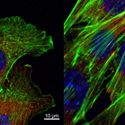

Stem Cell Research and Communicating Science

10/03/23 A distinguished pioneer in stem cell research for oral conditions, wound healing and diabetes explains the issues and the advances in this field, and the importance of science communication for the public. Jonathan Garlick